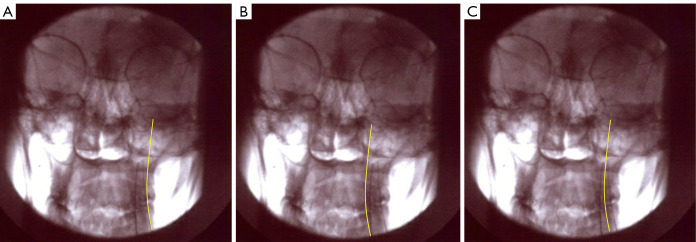

Background: This manuscript presents the challenges of treating various forms of headaches and the potential of interventional techniques targeting the greater occipital nerve (GON) to alleviate the burden on patients. Occipital neuralgia, characterized by stabbing or shooting pain in the base of the skull, is often associated with primary, cervicogenic, or migraine headaches. While occipital nerve blocks offer temporary relief, durable treatment options are limited. Pulsed radiofrequency (PRF) and thermal radiofrequency ablation (TRFA) have shown promise as minimally invasive procedures for long-term treatment. However, GON is not easily identified using ultrasound or fluoroscopic analysis; thereby, minimizing success of proper ablation. Here, the authors provide a percutaneous strategy to localize the GON and maximize lesion performance. We intend to provide an ex-vivo description of staggered bipolar radiofrequency (RF) lesioning and include the use of staggered bipolar lesioning of the GON and stimulation of the semispinalis capitis. We also analyzed the effectiveness and side effects from this ablation, retrospectively.

Methods: Patients with chronic refractory GON neuralgia were selected for GON TRFA. A novel double needle technique of sequential electrical stimulation was used to localize the GON and approximate needle to nerve distance. Once the needles were positioned adjacent to the GON, TRFA was performed using a bipolar staggered technique.

Results: Twenty-two patients with GON were treated with TRFA using a novel double needle technique. Seventy-two percent of these patients reported greater than 50% pain relief at both 1 and 6 months following the procedure. The results of our ex-vivo study demonstrate that performing TRFA using the parallel needle bipolar approach separated 8 mm apart produced the most desirable lesion dimensions that may correlate with effective ablation of the GON.